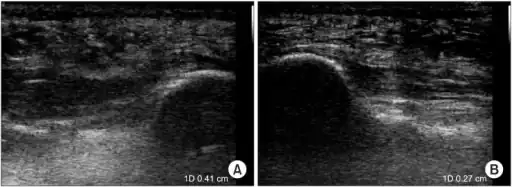

a)Ultrasonographic finding of plantar fasciitis b)normal sonographic finding

Thickened plantar fascia in ultrasound

The plantar fascia has three fascicles-the central fascicle being the thickest at 4 mm, the lateral fascicle at 2 mm, and the medial less than a millimeter thick.[18] In theory, plantar fasciitis becomes more likely as the plantar fascia's thickness at the calcaneal insertion increases. A thickness of more than 4.5 mm ultrasound and 4 mm on MRI are useful for diagnosis.[19] Other imaging findings, such as thickening of the plantar aponeurosis, are nonspecific and have limited usefulness in diagnosing plantar fasciitis.[13]